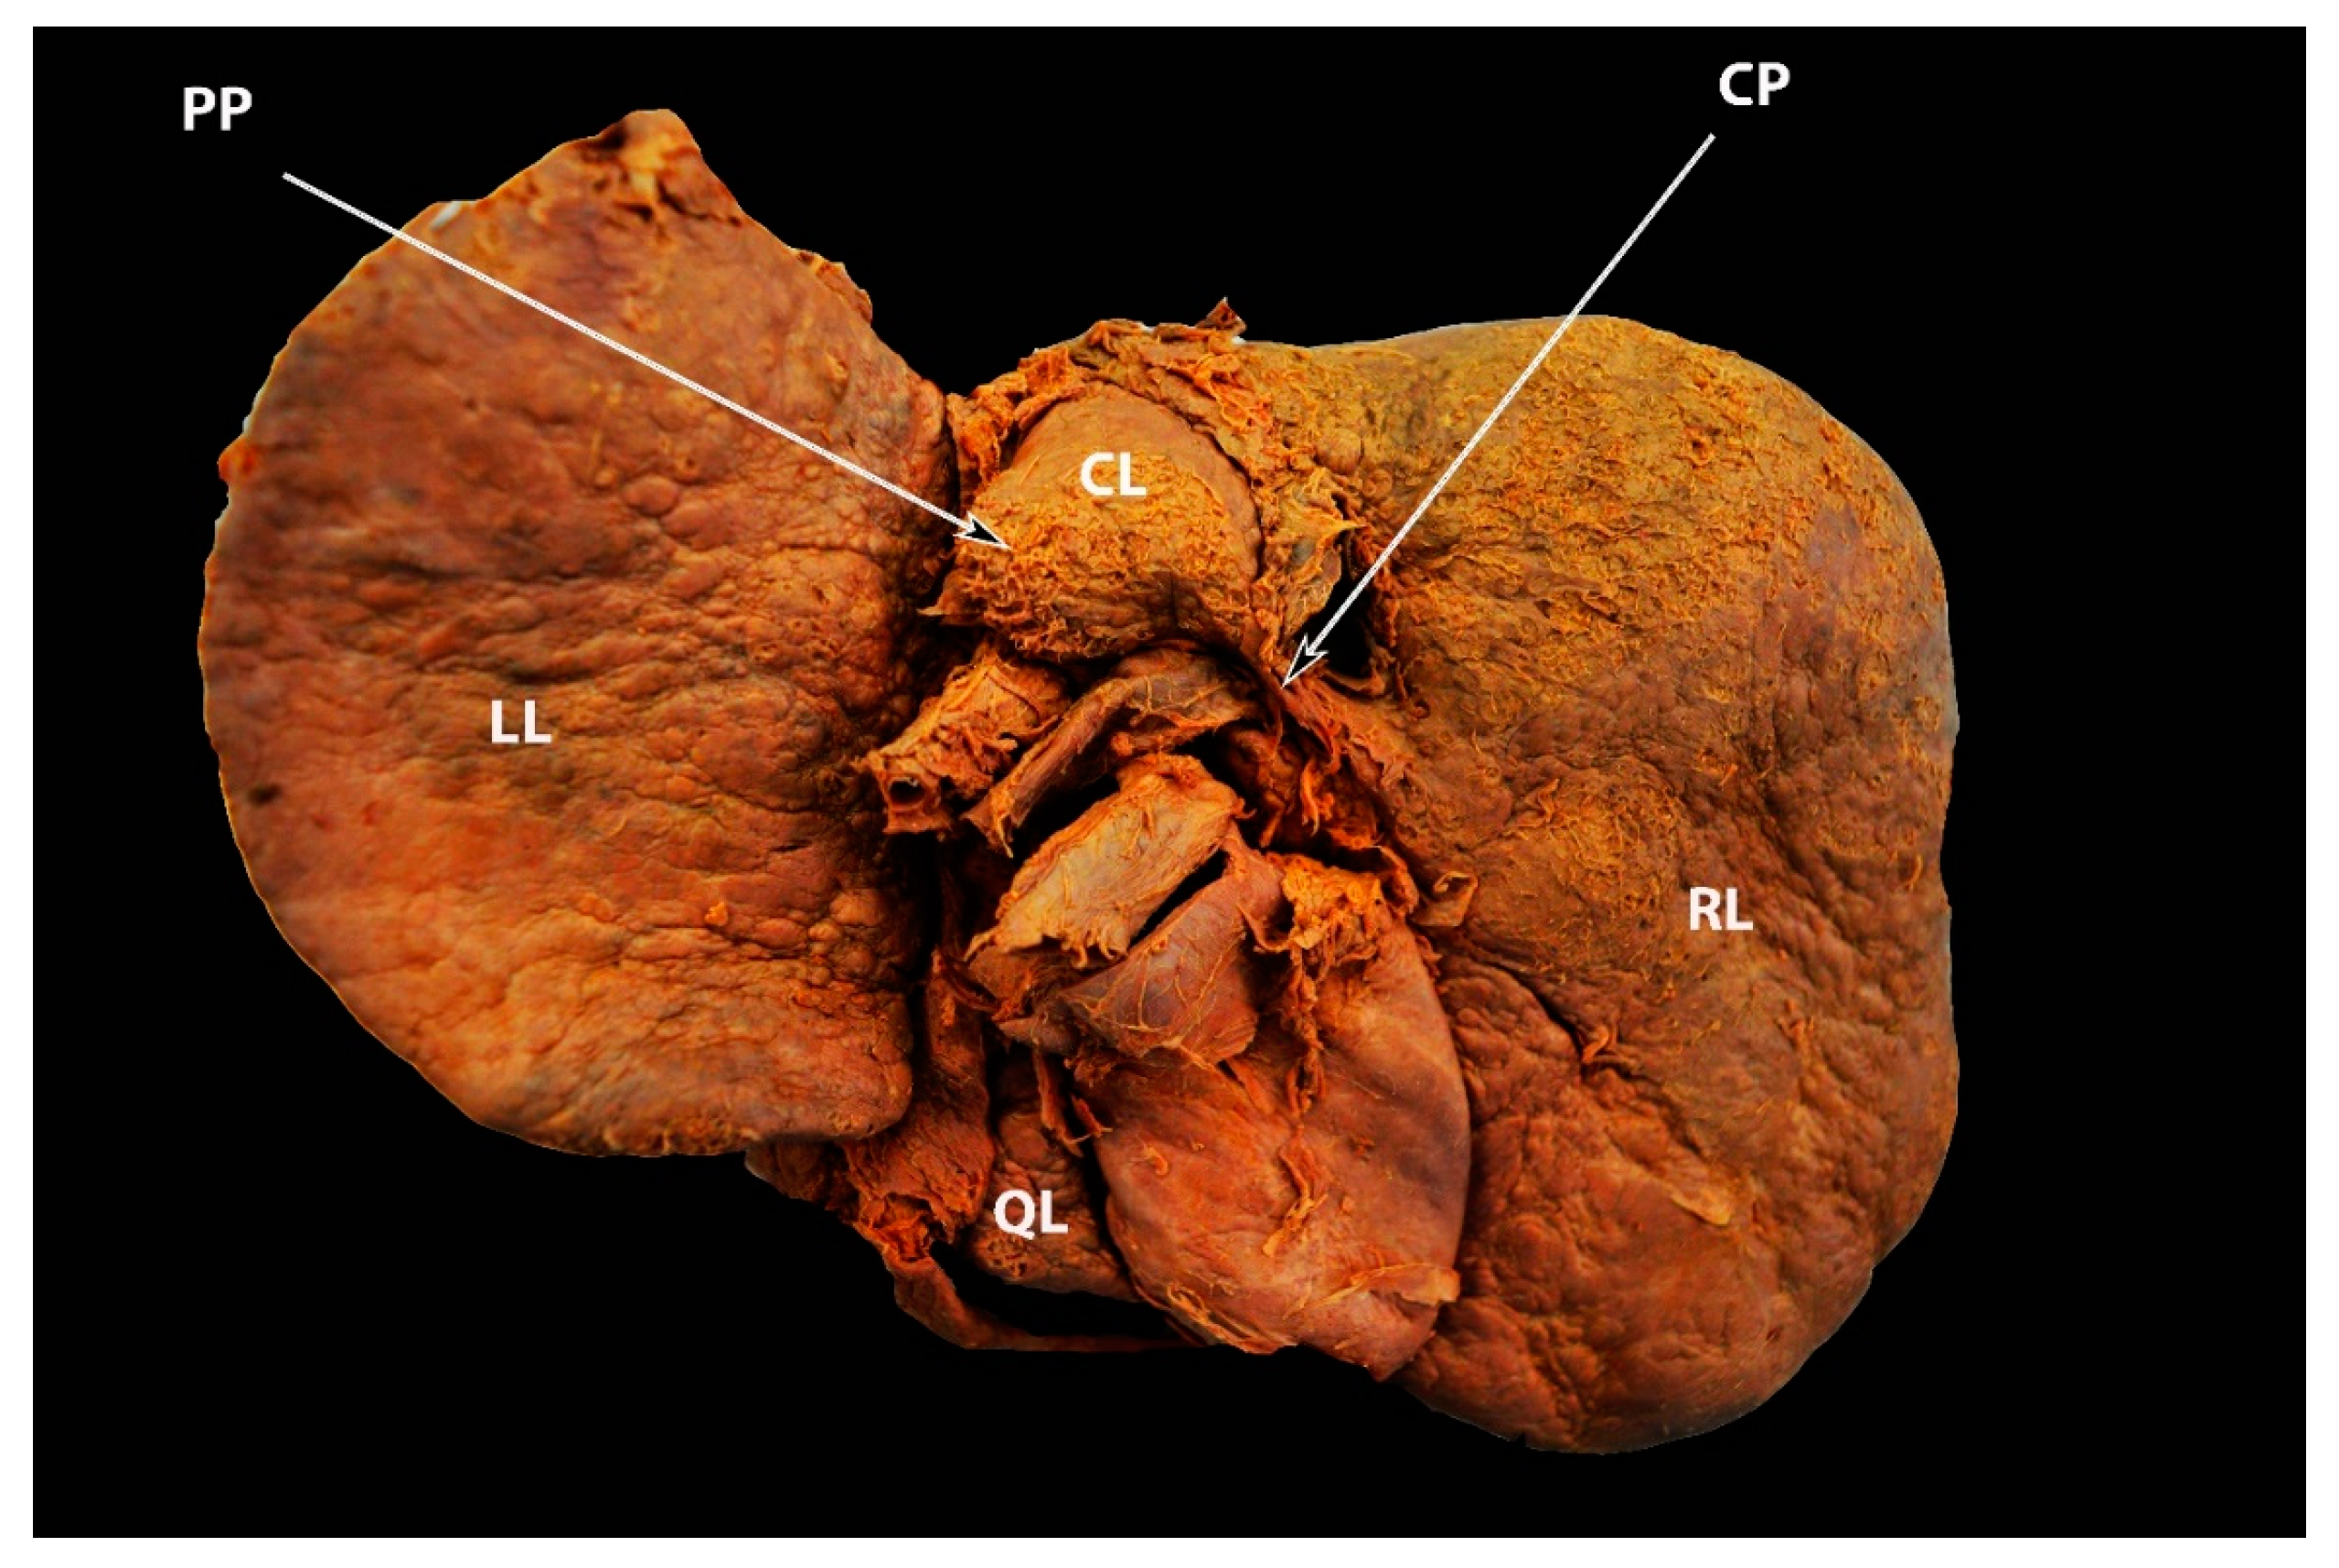

2. Anatomical Lobes of the Liver

3.4. Papillary Process (Spiegel’s Lobe) and Caudate Process of the Caudate Lobe

Significance of the Papillary Process (Spiegel’s Lobe) and Caudate Process of the Caudate Lobe of the Liver in Ovarian-Cancer Surgery